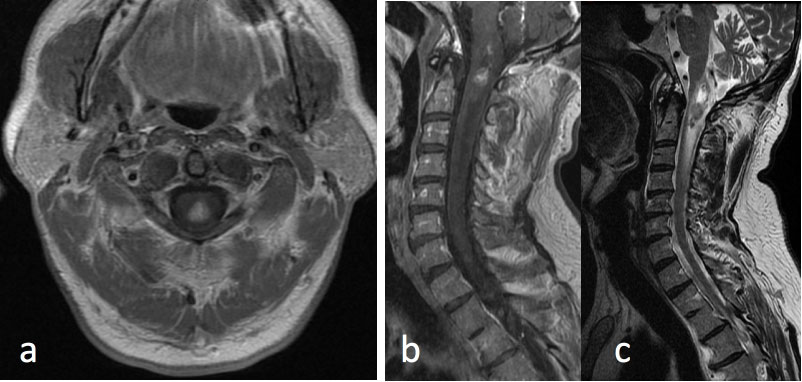

Figure 4: Spinal ependymoma.

MRI Cervical Spine: a) Axial T1 post-contrast at the level of the upper cervical spine; b) Sagittal T1 post-contrast; c) Sagittal T2 FSE.

61-year-old male with history of bilateral vestibular schwanomas and a heterogeneously enhancing mass within the upper cervical cord centrally with surrounding edema. Constellation of findings is consistent with Neurofibromatosis type II and the spinal lesion is a presumed spinal ependymoma.

They are iso- to hypointense on T1 weighted images and hyperintense on T2 weighted imaging. A cap sign, referring to low T2 signal intensity along the margins of the tumor, may be seen with spinal ependymomas and relates to hemosiderin deposition above or below the tumor from chronic hemorrhage of the lesion [9]. There can be considerable edema surrounding the tumor, best seen on the T2 weighted images. On diffusion weighted images, there is reduced diffusion, which relates to the tissue composition of ependymomas and their high cellularity [6] (Figure 4).